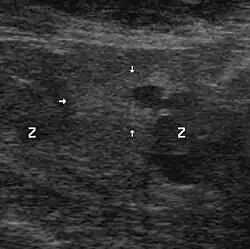

Ultraschall

Genauere Lokalisation und Größenbestimmung erlaubt die Ultraschalluntersuchung (transrektale Sonografie). Tumoren ab zehn Millimeter Durchmesser können damit zuverlässig gefunden werden, kleinere jedoch nur zu etwa 20 %.[54]